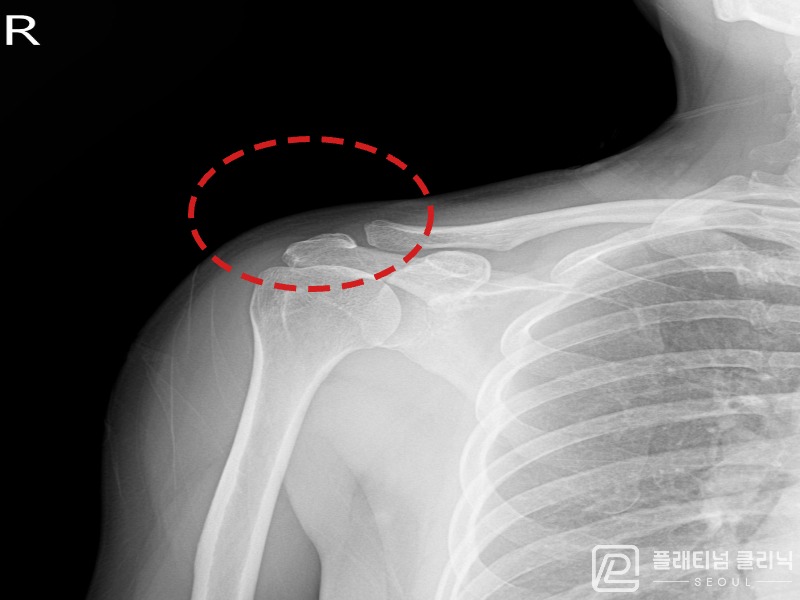

[촬영시기:21.11.04~21.11.09]

[석회분쇄흡입술] 우측 어깨 극심한 야간 통증으로 수면이 불가능해진 50대 여성 환자로, X-ray에서 우측 극상근건 내 석회 침착이 확인되어 석회분쇄흡입술을 시행하였습니다.